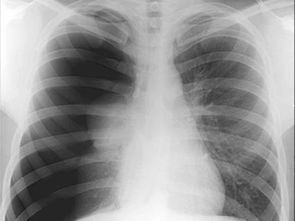

简单来说,气胸是指气体进入胸膜腔,造成积气状态,从而影响肺部正常功能的一种疾病。想象一下,你的肺就像一个充满空气的气球,而气胸就是这个气球破了一个小洞,里面的空气漏了出来,压到了周围的组织,导致呼吸困难甚至更严重的后果。

医生经过检查告诉我,我患上了自发性气胸。原来,这种病多发于体型瘦高、肺部发育较弱的年轻人身上,尤其是像我这样平时缺乏锻炼的人。医生还说,如果拖延治疗,可能会导致更加严重的并发症,比如张力性气胸,甚至危及生命。

在医院接受治疗的日子里,我深刻体会到了生命的脆弱和珍贵。医生为我进行了胸腔闭式引流术,将胸腔内的气体排出,帮助肺部重新扩张。整个过程虽然有些不适,但想到能够恢复健康,这些都显得微不足道了。